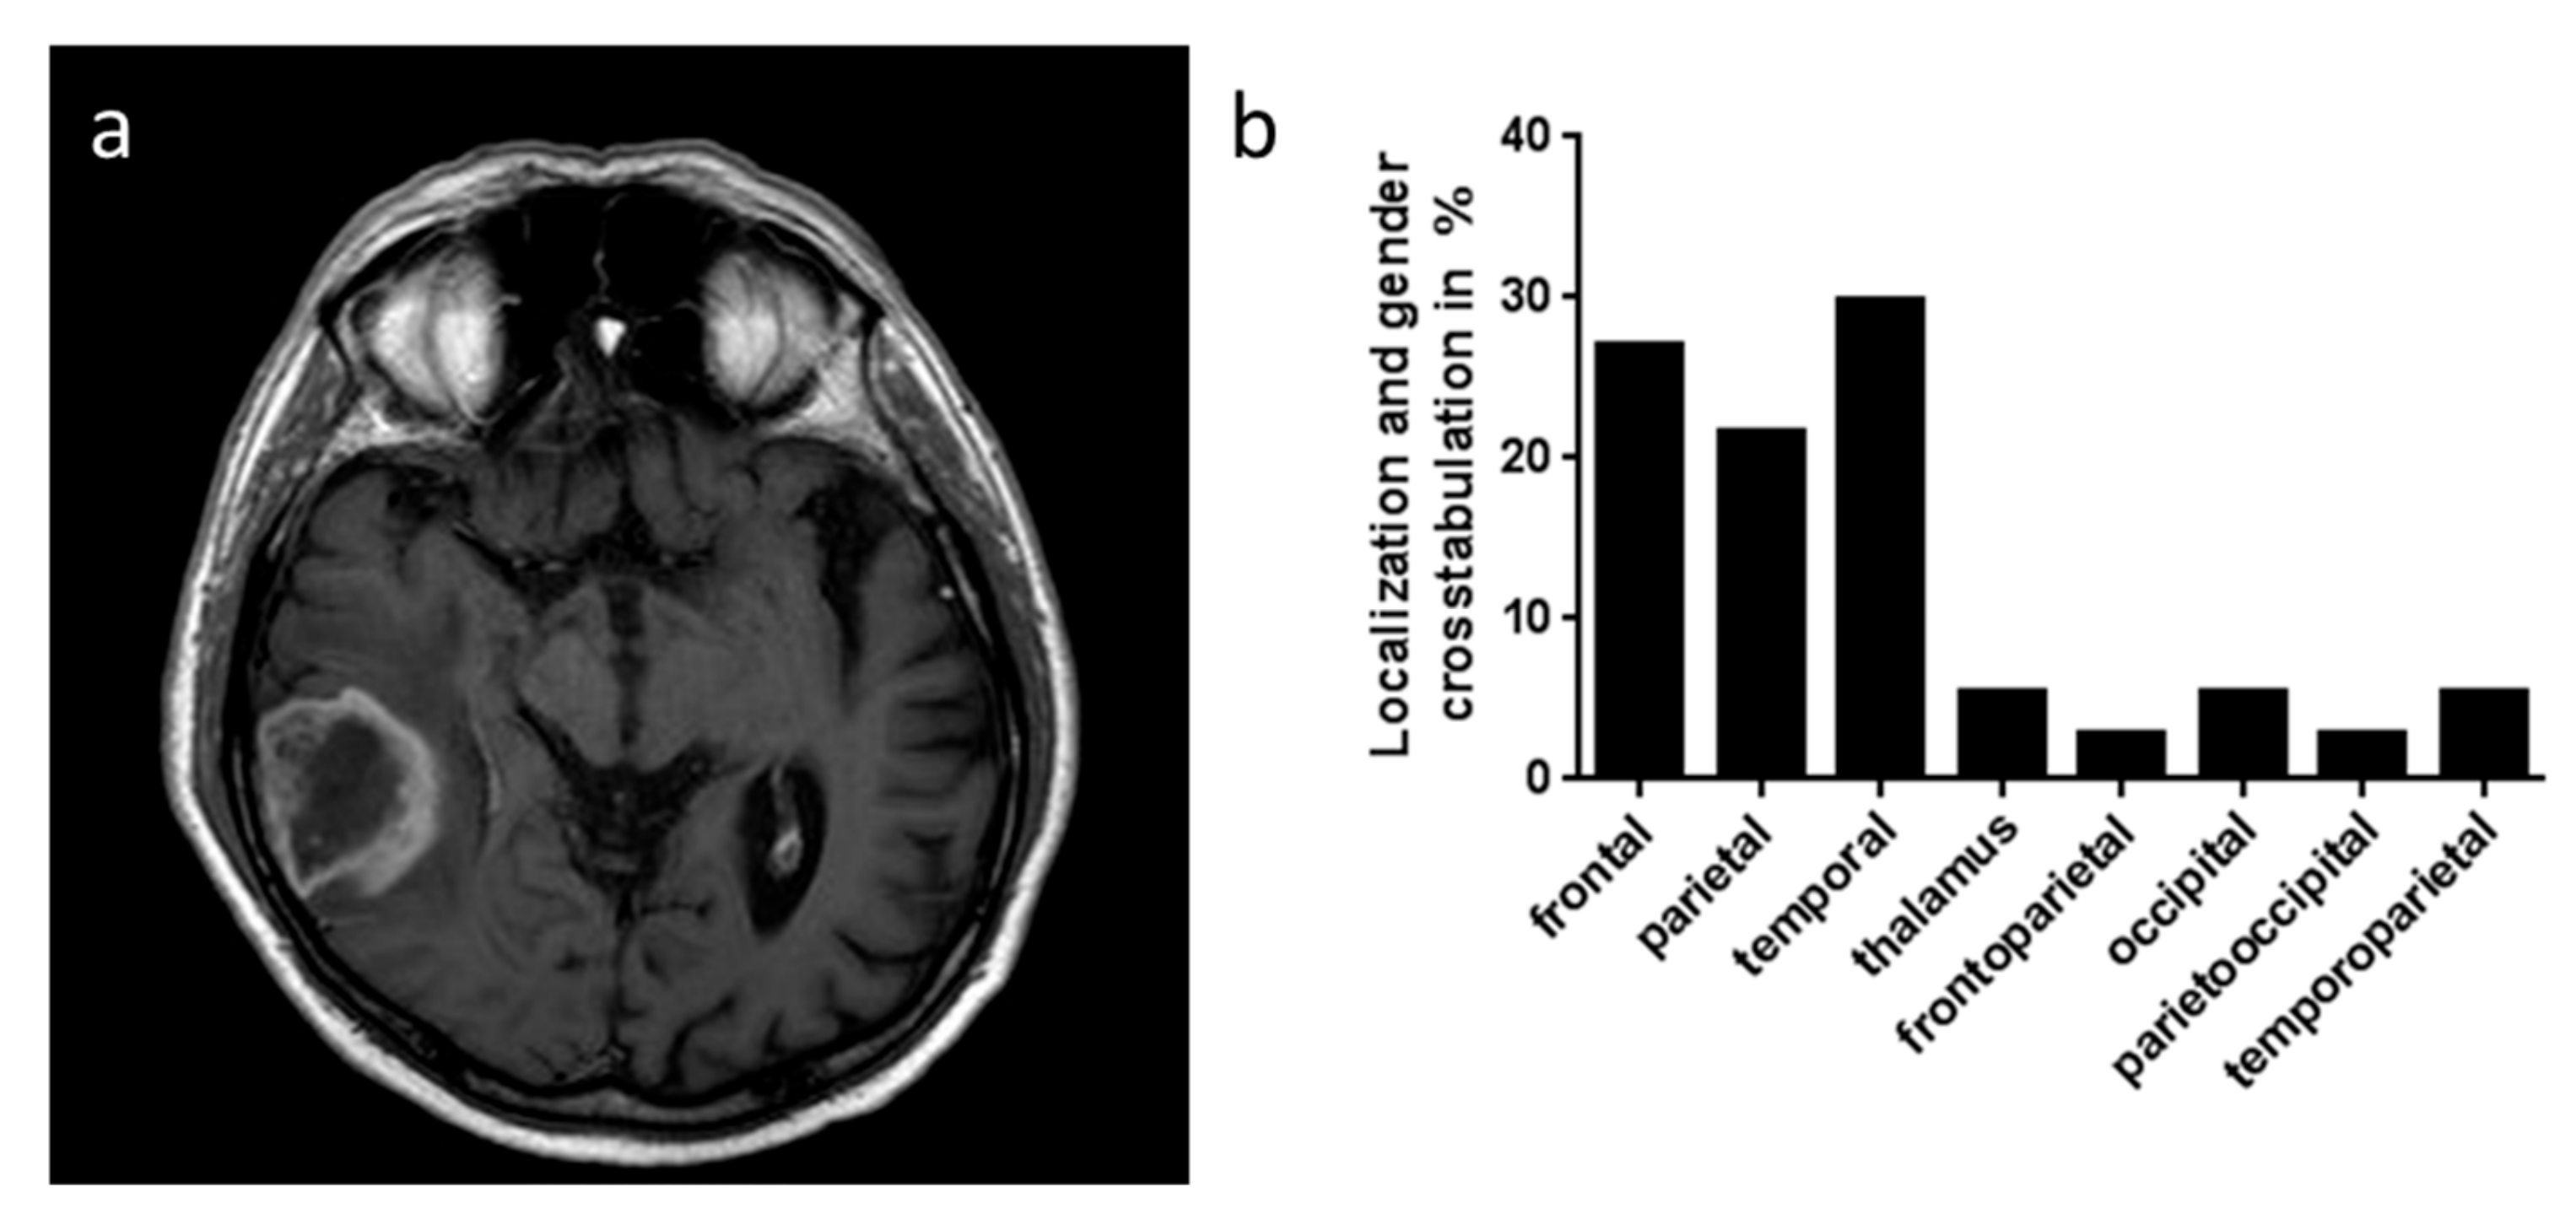

| Glioma Grade III and IV | Male | Female | Total | Lost To Follow Up |

|---|---|---|---|---|

| Number of patients | 26 | 11 | 37 | |

| Age at the onset mean±SD (yr.) | 69.05 ± 11.08 | 71.38 ± 11.72 | 68.78 ± 13.36 | |

| Side hemispheric | ||||

| right | 9 | 3 | 12 | |

| left | 17 | 8 | 25 | |

| bilateral | 0 | 0 | 0 | |

| Surgery | ||||

| resection | 19 | 3 | 27 | |

| biopsy | 7 | 8 | 10 | |

| First histological diagnosis | ||||

| grade IV | 23 | 10 | 33 | |

| grade III | 3 | 1 | 4 | |

| Localization | ||||

| frontal | 5 | 5 | 10 | |

| parietal | 6 | 2 | 8 | |

| temporal | 9 | 2 | 11 | |

| thalamic | 2 | 0 | 2 | |

| fronto-parietal | 0 | 1 | 1 | |

| occipital | 2 | 0 | 2 | |

| perieto-occipital | 0 | 1 | 1 | |

| temporo-parietal | 2 | 0 | 2 | |

| Radiation therapy | 20 | 9 | 29 | 3 |

| Chemotherapy | 20 | 6 | 26 | 5 |

| Survival mean ± SD (mon.) | 11.68 ± 15.22 | 9.38 ± 4.98 | 11.07 ± 13.27 | |